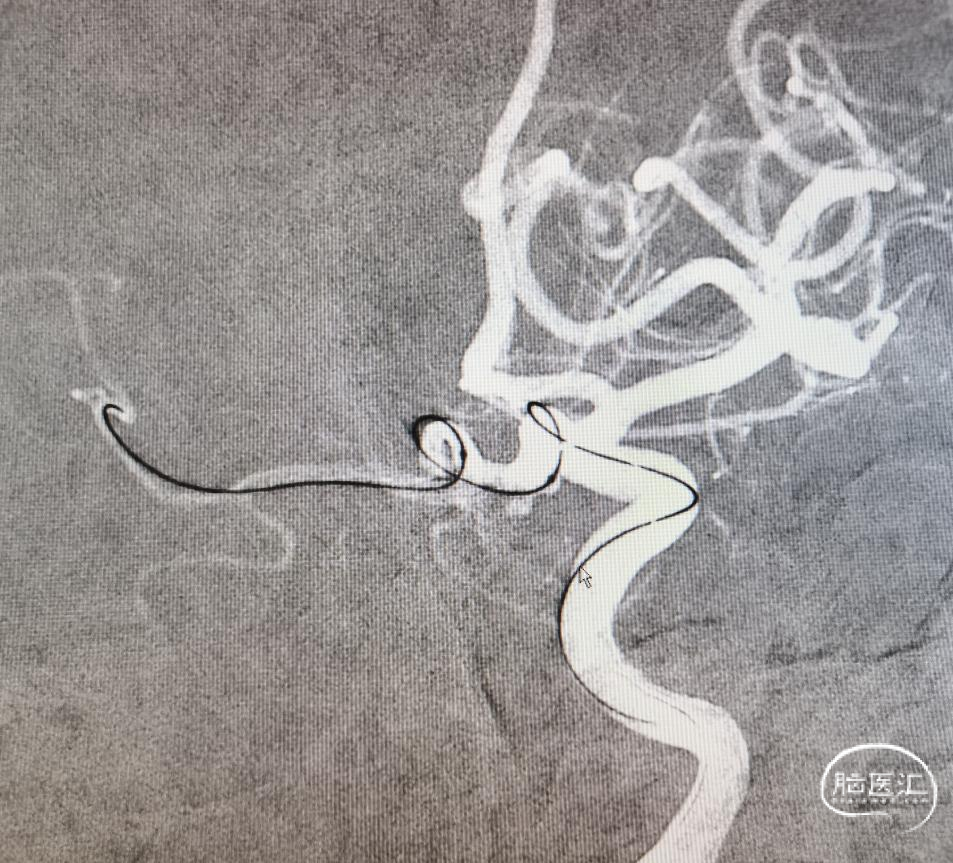

第二次

两次角度就差了一点点,结果截然相反,真是个“差之毫厘谬以千里”啊。剩下的工作就简单了。

圈已到位,准备压个支架。在后交通动脉起始处再放个圈,加强防护,防止复发。

直接放上支架,虽然支架留到颈内动脉,但是如果摆尾不好,后果还是比较惨的,因此选择了一条比较安全的方案。手术顺利。